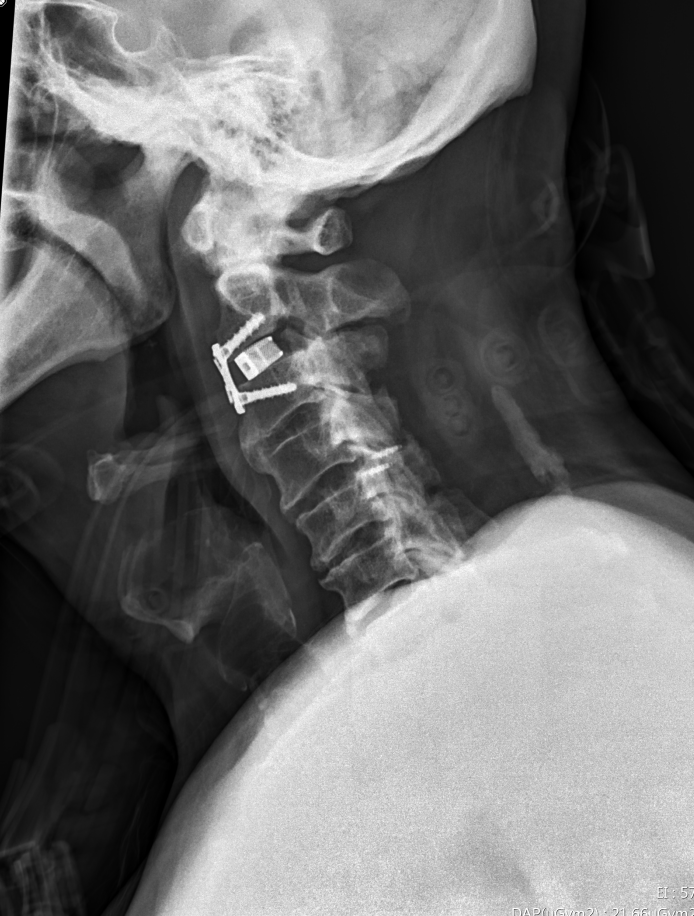

洪祥益主任進一步指出,只剩下從頸椎前面做微創手術, 頸椎第二節、三節的位置很高,幾乎從頸椎深入到口腔的高度, 在顯微鏡下,精準地用電鑽把骨刺全部磨乾淨, 再以骨釘固定及骨融合手術; 磨骨刺的過程有點像一塊石頭壓在豆腐上,要以電鑽把石頭磨掉, 風險極高,而執刀醫師必須要很輕巧、不能太用力, 這是最困難的地方,特別是這骨化的韌帶比骨頭還硬, 稍微不慎即可能造成癱瘓, 也因此花蓮慈院神外團隊的脊椎手術全程均有神經監控, 再加上有顯微鏡放大監看,讓手術更安全, 醫師也可較放心的執行術式。

圖:醫師精準的用電鑽把骨刺全部磨乾淨,再以骨釘固定及骨融合手術。